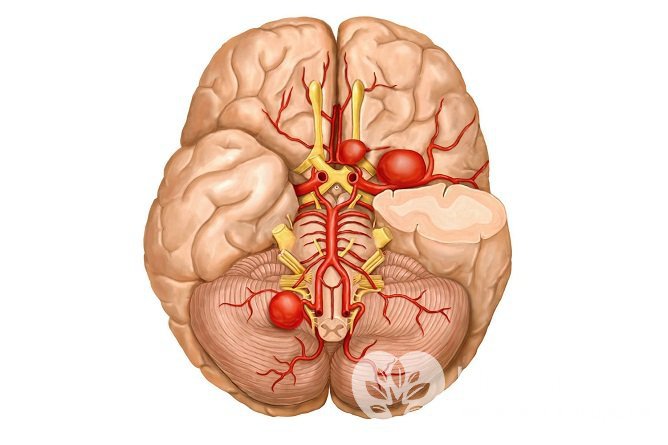

Несколько аневризм, расположенных на разных артерияхВ зависимости от формы аневризмы сосудов головного мозга могут быть веретенообразными и мешотчатыми. Вторая форма встречается примерно в 50 раз чаще, чем первая.